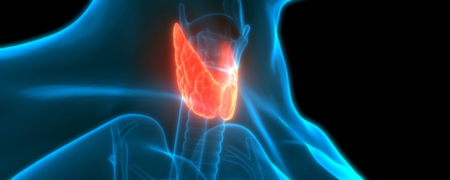

بیماری کم کاری تیروئید به ندرت علائم مشهود از خود بروز می دهد، اما همین علائم نامرئی می تواند شما را ناتوان کند! مگر اینکه بتوانید به درستی این بیماری...

علامت هشداردهنده بیماری نامرئی کم کاری تیروئید که فقط صبحها ظاهر میشود